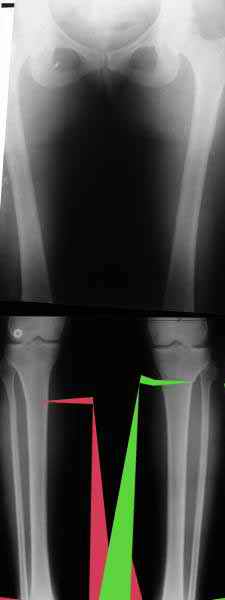

AC> Вот, с учетом и без учета, и на разных уровнях...

AC> Саша Артемьев, может, для данного случая свой вариант нарисуешь?

Из приведнной схемы не совсеим понял что означают разноцветные линии.

И зачем латерализация периферического фрагмента. Я всегда делаю медиализацию. См схему. И для данного случая медиализация подходит как нельзя лучше.

a> Я всегда делаю медиализацию. См схему. И для данного случая

Медиализация - это чисто эстетический прием, как я понимаю. Поскольку если делать остеотомию ниже вершины деформации, для восстановления оси надо делать смещение по ширине, в данном случае как раз латерализацию.

А вот на схемке без осей - там на разных уровнях (который правильнее?) устранение варуса чисто открытым клином без медиализации-латерализации. Если как-то так сделать - этого недостаточно будет?